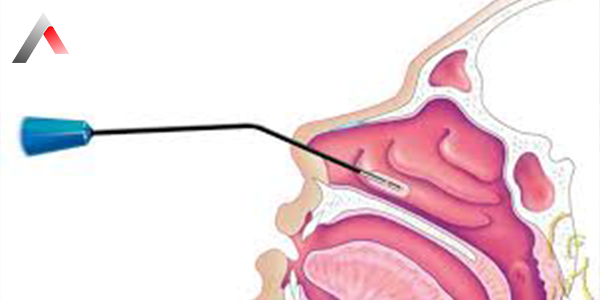

One of the most commonly preferred methods for treating concha hypertrophy is nasal polyp ablation surgery. This procedure is usually performed under local anesthesia and takes approximately 15–20 minutes. During the surgery, the overgrown part of the nasal turbinates is reduced using radiofrequency, laser, or electrical energy. This opens the nasal cavity and facilitates airflow.